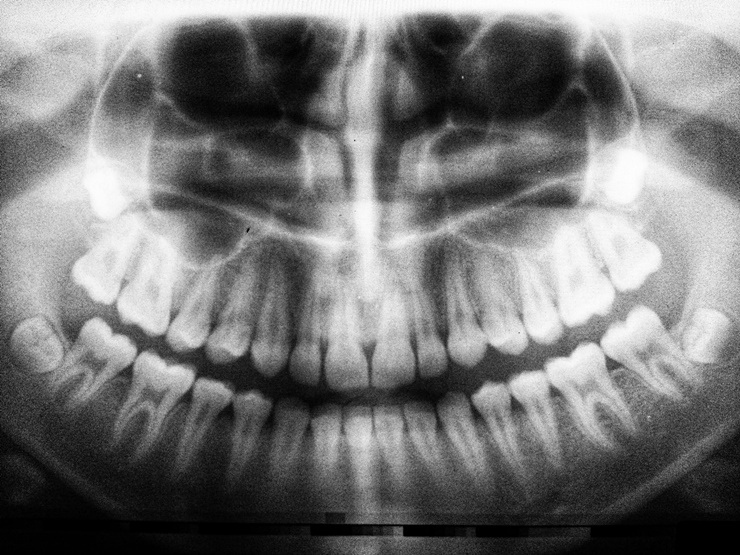

치과 임플란트는 인공 치아를 지지하기 위해 턱뼈에 외과적으로 부착되는 기둥이다. 신경을 되살리지 못하는 경우에, 임플란트를 하게 되는데 뼈 또한 부족하다면 임플란트 인공뼈 이식 과정을 진행하게 된다. 치과 임플란트 경우 성공률이 높지만 일부 사람들은 임플란트 실패를 경험하기도 한다.

임플란트 인공뼈 이식 후, 약 5~10%가 시술 직후 또는 수개월 또는 수년 후에 실패하는 것으로 밝혀졌다. 임플란트 수술 및 인공뼈 이식 전에 알아야할 6가지 사항에 대해서 알아보도록 하자.

성공적인 시술은 임플란트를 지지하기 위한 턱뼈가 중요하다. 뼈가 충분하지 않는 경우 인공뼈를 이식이 가능하다. 그러나, 골다공증으로 골 손실이 발생하는 경우도 있는데, 해당 상태는 골밀도가 감소할 때 발생한다.

뼈가 약해지고 골절 위험이 증가하며, 심한 잇몸 질환의 경우 입안의 뼈를 악화시키는 경우도 대부분이다.